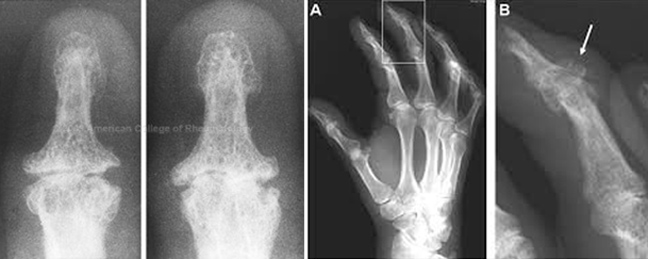

Heberden Ρευματοειδής αρθρίτιδα

Οι μικρές αυτές διογκώσεις εμφανίζονται μόνο στις αρθρώσεις των δακτύλων και δεν αφορούν την άρθρωση δακτύλων-μετακαρπίων. Οι πρησμένες αρθρώσεις μετακαρπίων-δακτύλων οφείλονται σε ρευματοειδή αρθρίτιδα (R.A.) που προκαλεί μεγάλες αλλοιώσεις και παραμορφώσεις και σε άλλες αρθρώσεις, μεγάλες (γόνατα, αγκώνες, καρπούς).